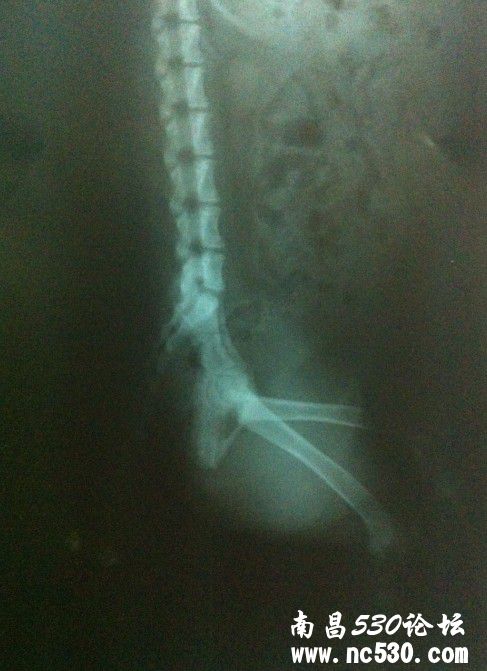

[疾病诊断] 是不是CHD病,附上X光片。

是不是CHD病,附上X光片。

动物品种:边牧

动物年龄:5个月

动物性别:雄

食欲如何:正常  排便如何:正常  狗狗走路的时候左腿明显会往外拐,感觉就像是脚踝那边脱节一样,从脚踝到膝盖会往外拐出似的,小步慢跑的时候看不出,但是会明显听到脚趾擦地的声音(不是很频繁),快跑的时候看不出异样。正常站立的时候双腿站的不是很直。  吃了1个星期的关节生,每天2次,每次1片,没有明显改善,不知道是不是用量不够?非常担心狗狗,希望能帮帮我,狗狗到底是怎么了?谢谢了~~~~谢谢